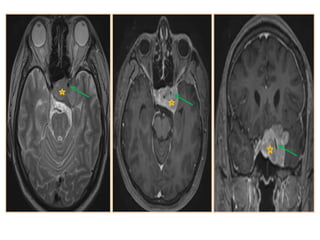

• #42 Chordoma: mass centered on the clivus and the right cavernous sinus, heterogeneously hyperintense on T2-wi. (a), hypo- to isointense on T1-wi with an heterogeneous enhancement after contrast (b) corresponding to a chordoma.